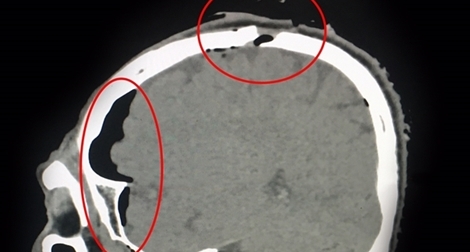

Sau cơn đau đầu dữ dội, nhập viện phát hiện khối máu tụ dưới màng cứng

16:48 13/07/2017

Chiều 13-7, nguồn tin từ Bệnh viện Đa khoa Xuyên Á (BVXA) cho hay, các bác sĩ tại đây đã chẩn đoán chính xác và phẫu thuật thành công lấy trọn được khối máu tụ dưới màng cứng cho cụ ông B.V.M. (72 tuổi, ngụ tại huyện Dương Minh Châu, Tây Ninh) .Điều mà các bác sĩ và gia đình cũng cố gắng tìm hiểu, đó là không hiểu do cụ ông bị té, ngã từ bao giờ hay bị bệnh lý mạch máu não từ trước mà sinh ra khối máu tụ màng cứng mãn tính.